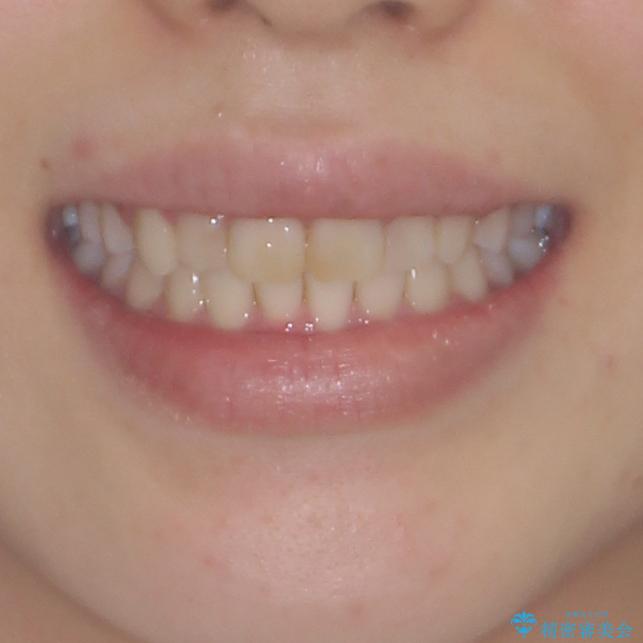

気になる前歯を治したい インビザラインで気づかれずに矯正治療

- ワイヤーではない矯正治療があると聞いたとのことで来院された患者様です。

長年前歯のデコボコを気にしていたもののワイヤー矯正に抵抗があり躊躇していたそうですが、インビザラインなら治療してみたいとのことで相談にいらっしゃいました。

インビザライン適用の歯列であったため、歯と歯の間を削るIPRを用いて改善することとしました。

お仕事柄、長時間のマウスピース装着が苦ではなかったので、歯列はすぐに整いましたが、ゆっくりとした交換頻度であったので、2年ほどの治療期間を要しました。